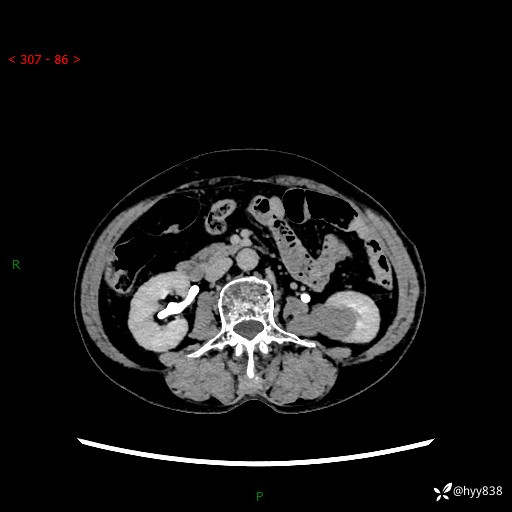

72岁/女,检查发现左肾占位1天。为了满足诊断,常规四期后,又加了延迟期-结果公布~

【患者信息】:72岁/女

【主诉】:检查发现左肾占位1天

【现病史及既往史】:患者于1天前检查发现左肾占位,无畏寒发热,无咳嗽咳痰,无腰腹部疼痛不适,无肉眼血尿、无尿频尿急症状,起病来,患者未行特殊治疗,为求进一步诊治,门诊以"左肾占位"收治入院。 发病来患者精神、饮食、睡眠良好,小便如上,大便正常,体重无明显变化。

【检查】:肾脏CT平扫+增强